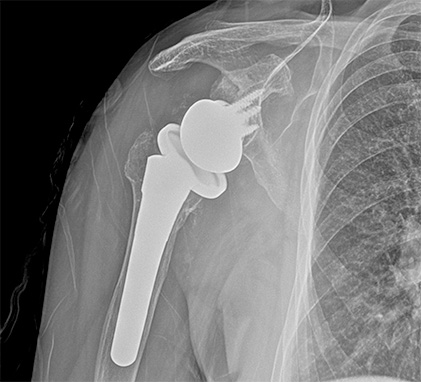

어깨 관절

인공관절치환술